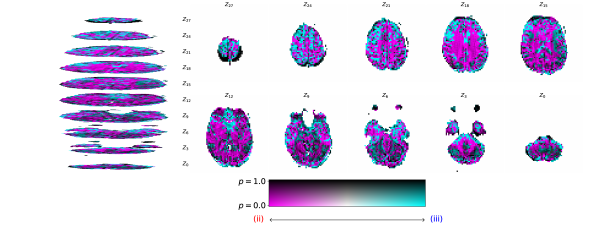

Figure 2 illustrates the distribution of residues (observed vs. estimated differences) on the fMRI volumes for the NODDI dataset. Clearly, by visual inspection, (iv) model has the darker and biggest area of shaded regions, which implies a better coverage across the brain regions and better synthesis quality. Models with topographical attention, (ii) and (iv), corresponding to Figures 2(b) and 2(d), respectively, significantly improve the synthesis, as shown by the darker and bigger areas against (i) and (iii) depicted in Figures 2(a) and 2(c), respectively. Particularly, we notice that models (i) and (iii) report difficulty in the retrieval of haemodynamical activity located in occipital and parietal lobes.

To better address which regions our baselines had more difficulty retrieving, the normalized residues were computed and are illustrated in Figure 3. Baselines – corresponding to models (i) and (ii), shown in Figures 3(a) and 3(b) respectively, which correspondingly implement a linear projection in the latent space and topographical attention –, have difficulty retrieving the prefrontal, occipital and parietal lobes, as the shade tends to a lighter grey in that region. Model (iv), shown in Figure 3(d), does not show a noticeable region with a lighter tone of grey, which implies no evident difficulty in retrieving haemodynamical activity across the different brain regions.